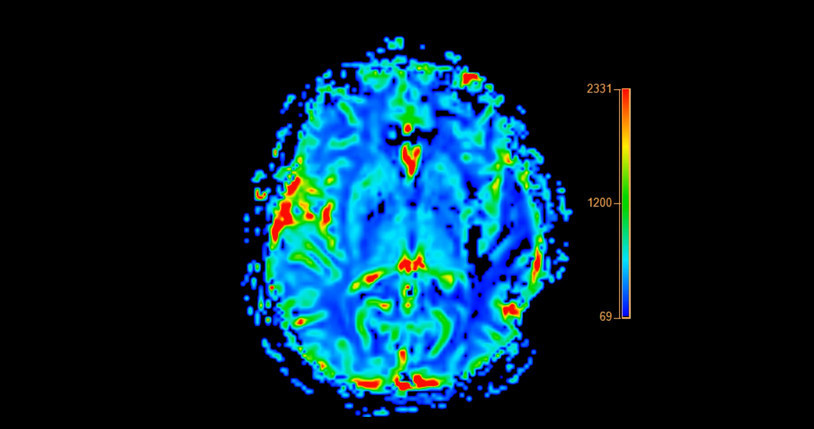

Araştırmacılar, bir sonraki adım olarak nörogörüntüleme yöntemleriyle plazmadaki tau artışının beyindeki tau birikimiyle bağlantısını incelemeyi planlıyor. Çalışma ekibi, katılımcıların genellikle temel hizmetlerde çalışan kişiler olduğunu ve bu nedenle virüse daha fazla maruz kalmış olabileceklerini belirterek, sonuçların genel nüfusu birebir yansıtmayabileceğini vurguluyorlar.